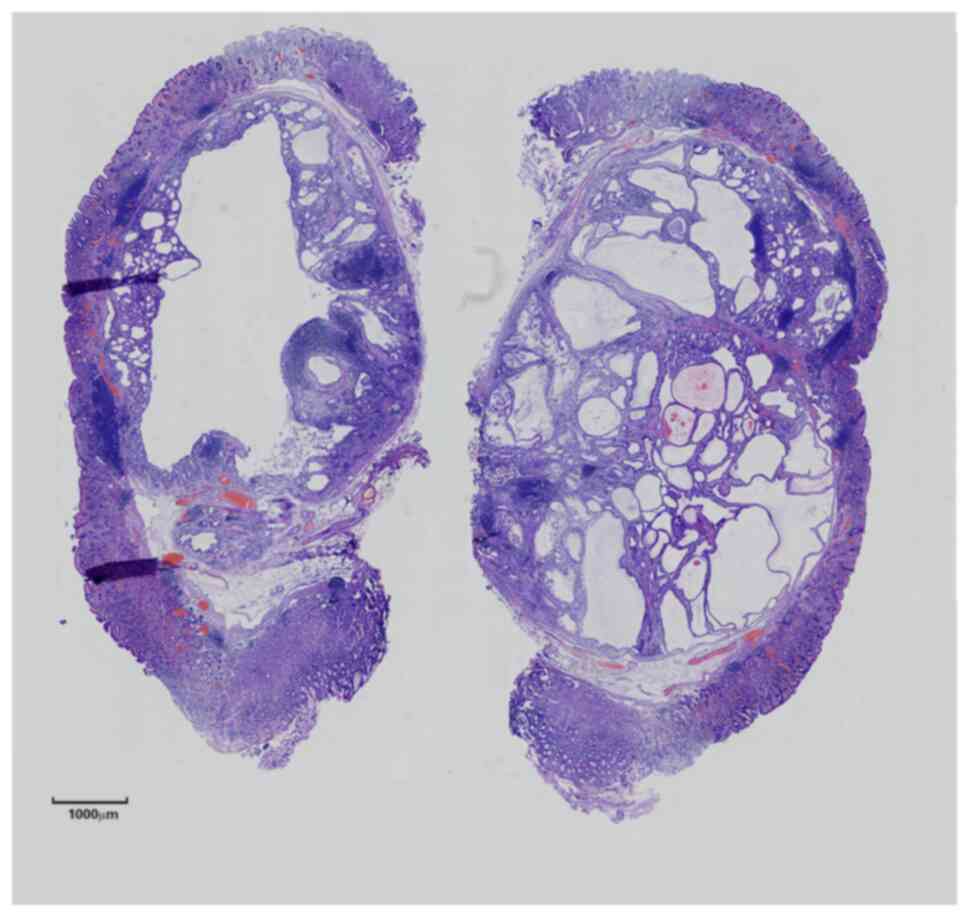

Gastric inverted hyperplastic polyp: A case report

Inverted hyperplastic polyp (IHP) is a rare disease characterized by the downward growth of proliferative mucosal components into the submucosal layer. It is often misdiagnosed as other submucosal tumors and accurate diagnosis requires pathological examination. Most patients with IHP have no clinical symptoms and some have non‑specific symptoms, such as abdominal distension, abdominal pain and even anemia. IHP is treated via endoscopic mucosal resection or endoscopic sub‑mucosal section. The present study reported a case of IHP and discussed its clinical manifestations, clinicopathological diagnosis, differential diagnosis and treatment to improve our understanding of the disease.

Figure 1

Figure 2

Figure 3

Figure 4

Figure 5

Figure 6

Figure 7